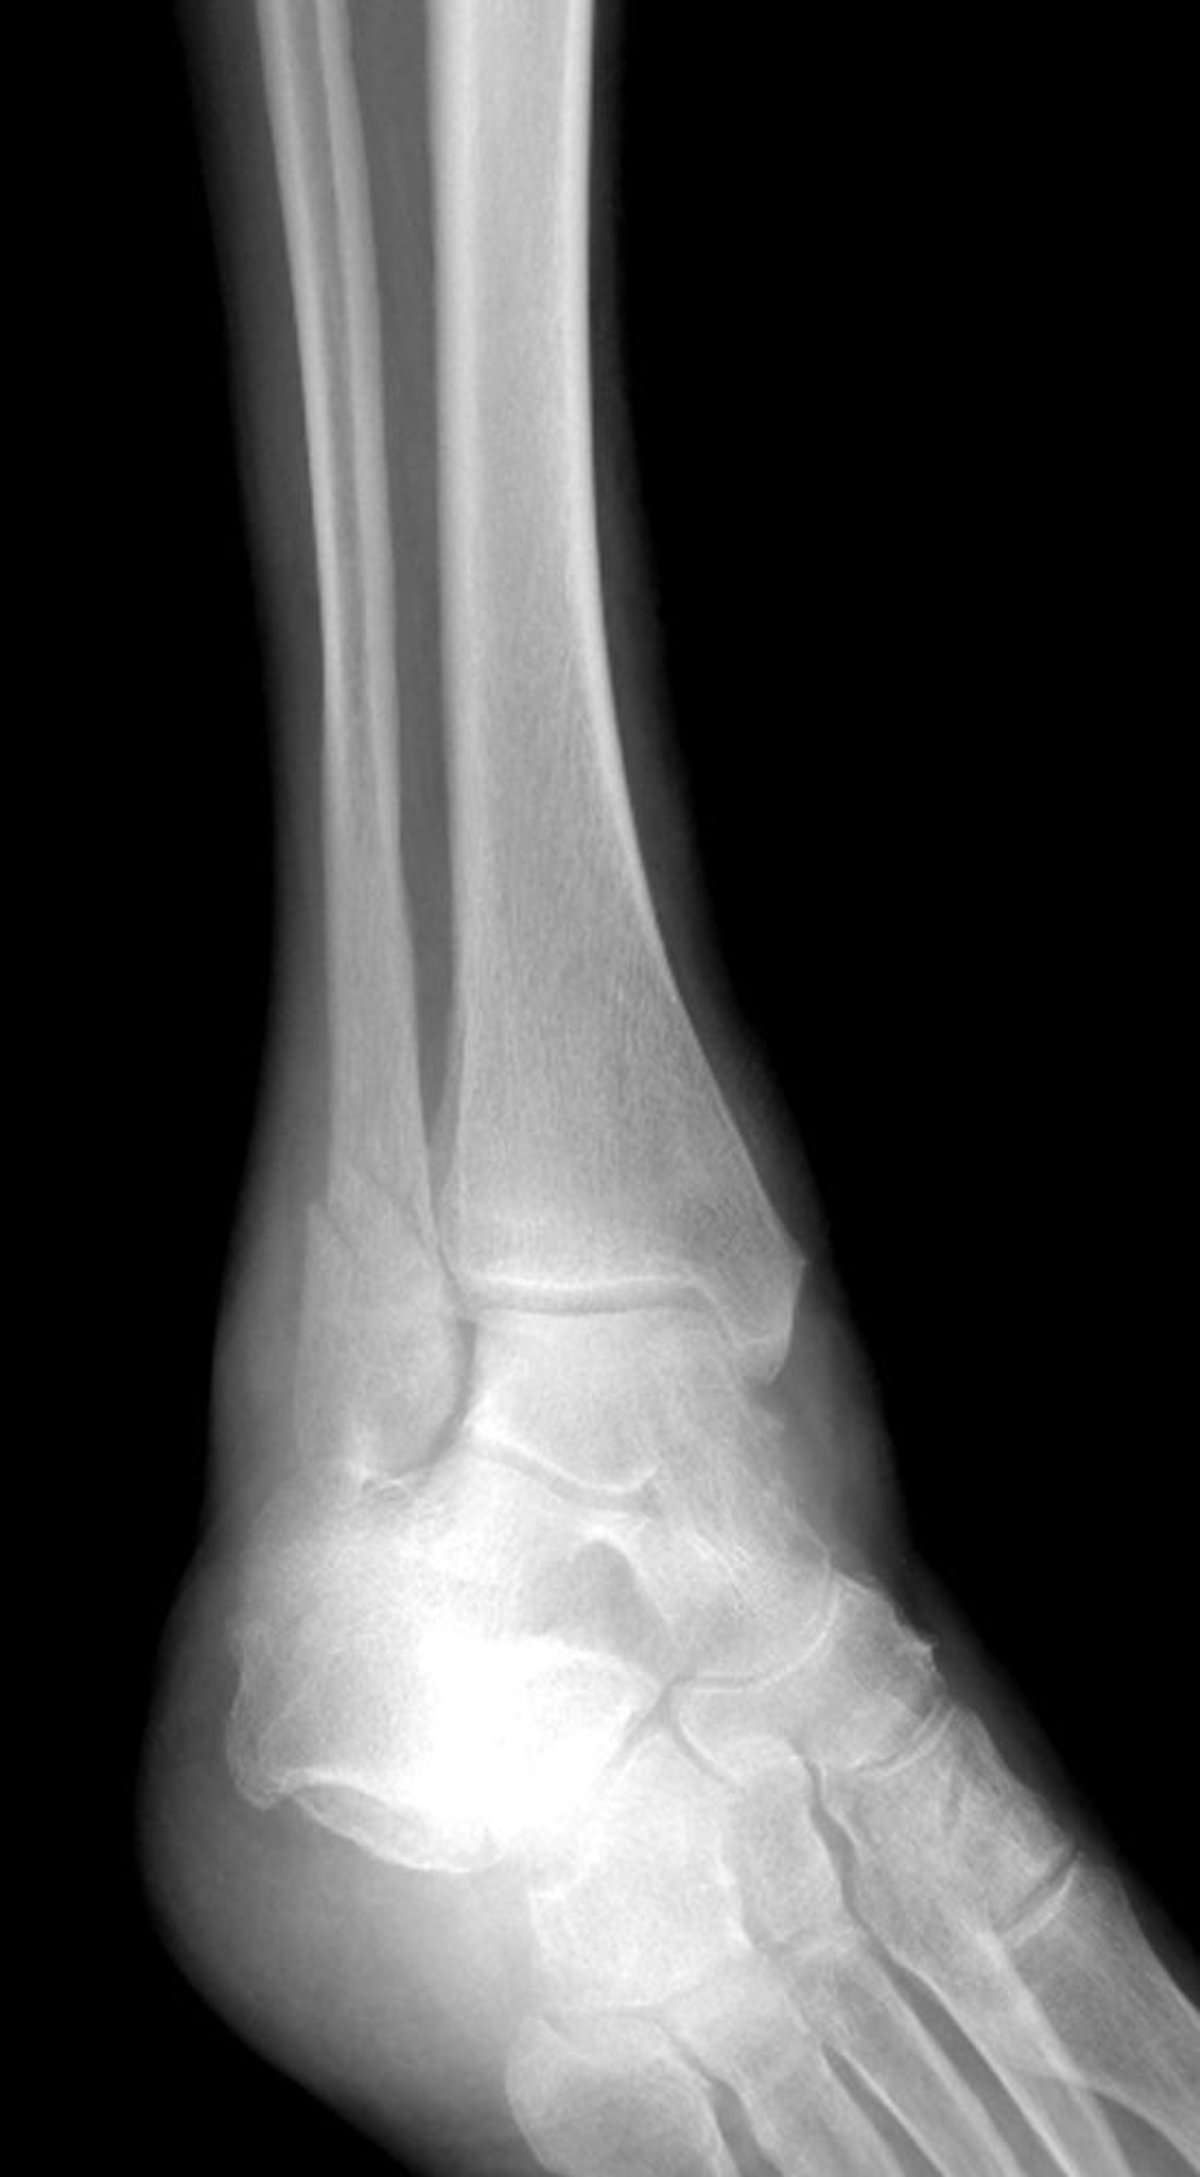

Frattura del malleolo laterale

Questa frattura della caviglia colpisce il malleolo laterale, ma risparmia il malleolo mediale.

LIVING ART ENTERPRISES, LLC/SCIENCE PHOTO LIBRARY